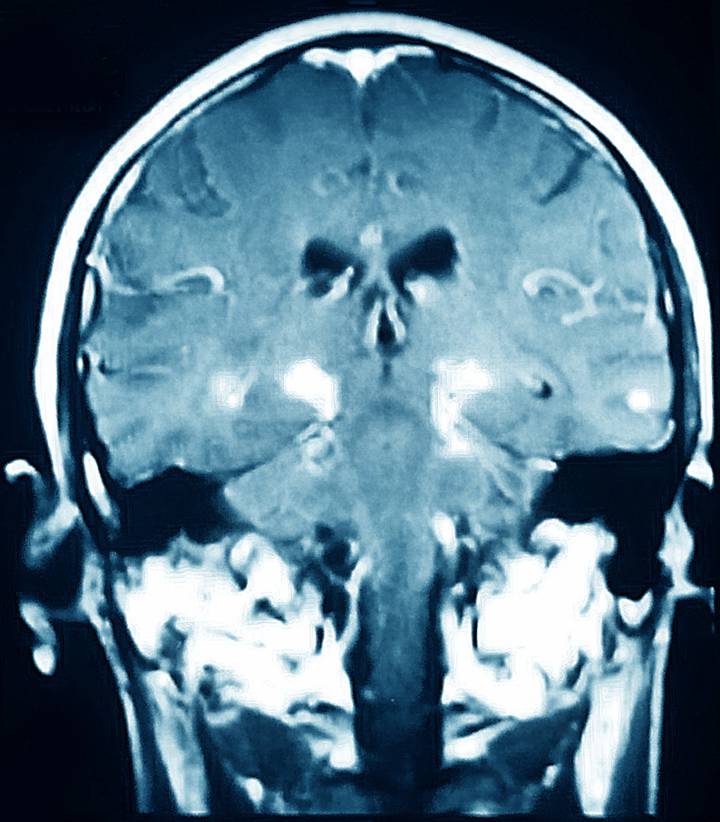

¿Son reversibles los daños cerebrales del párkinson?

En la enfermedad de Parkinson se produce una pérdida irreversible de dopamina en el cerebro como consecuencia de la degeneración neuronal. Leer más >>